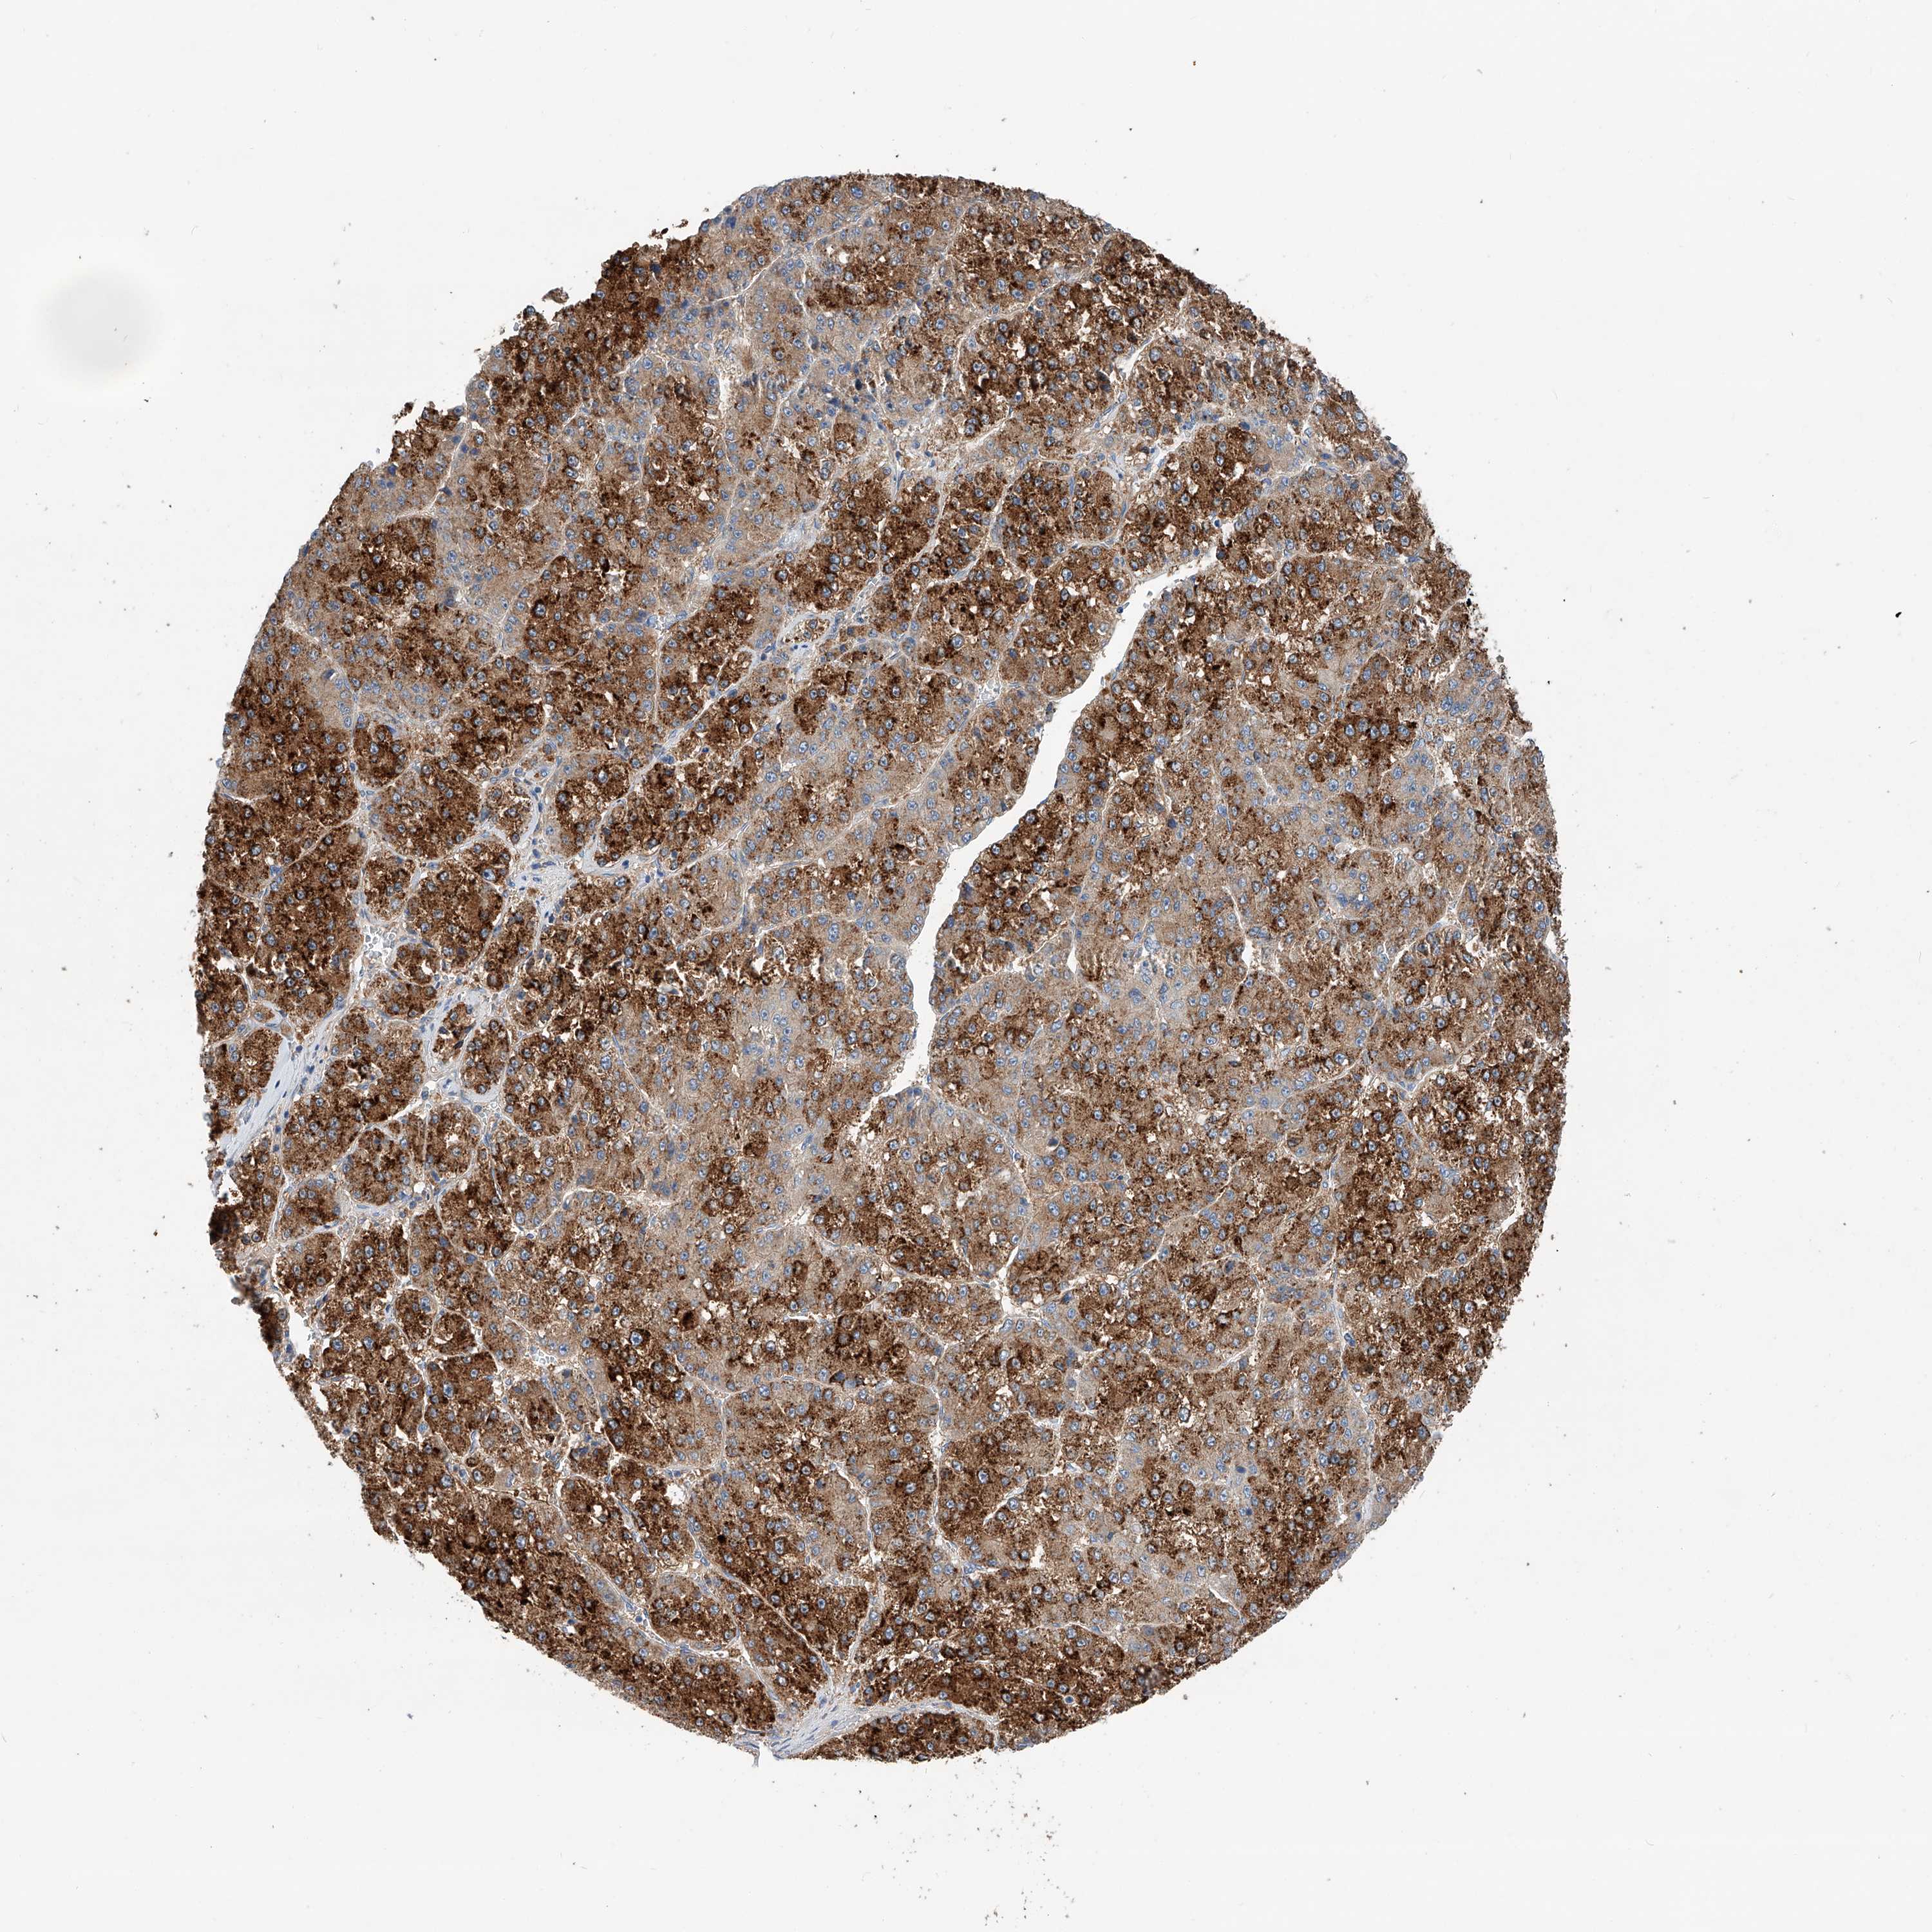

LIVER CANCER - Protein expressioni

A mouse-over function shows sample information and annotation data. Click on an image to view it in a full screen mode. Samples can be filtered based on level of antibody staining by selecting one or several of the following categories: high, medium, low and not detected. The assay and annotation is described here.

Note that samples used for immunohistochemistry by the Human Protein Atlas do not correspond to samples in the TCGA dataset.

Antibody stainingi

Antibody staining in the annotated cell types in the current human tissue is reported as not detected, low, medium, or high, based on conventional immunohistochemistry profiling in selected tissues. This score is based on the combination of the staining intensity and fraction of stained cells.

Each image is clickable and will lead to virtual microscopy that enables deeper exploration of all samples and also displays staining intensity scores, fraction scores and subcellular localization as well as patient and tissue information for each sample.

Antibody HPA030220

Staining

High

Medium

Low

Not detected

Intensity

Strong

Moderate

Weak

Negative

Quantity

>75%

75%-25%

<25%

None

Location

Nuclear

Cytoplasmic/membranous

Cytoplasmic/membranous,nuclear

Cholangiocarcinoma

Carcinoma, Hepatocellular, NOS